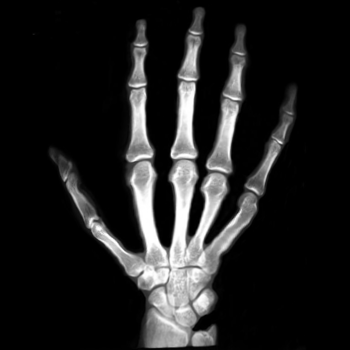

Figure 7. The first hand X-ray example.

After testing our proposed method on several synthetic images, we now consider applying it on real medical images. Here, we consider a hand X-ray image as the source image (Fig. 7(a)) and a deformed hand X-ray image as the target image (Fig. 7(b)). Fig. 7(c) shows the original absolute intensity difference between the two images. It can be observed that different fingers are displaced in a nonuniform manner (for example, the displacement of the index finger is much larger than that of the little finger), while the wrist remains almost the same. Therefore, a simple rigid transformation is insufficient for yielding a good registration. As shown in Fig. 7(d), our proposed method successfully deforms the source image to match the target image, and the final intensity difference is significantly smaller (see Fig. 7(e)). From the deformed underlying grid in Fig. 7(f), it can be observed that the mapping is smooth and bijective. For comparison, both LDDMM [5] and DDemons [47] fail to register the fingers and are non-bijective (see Fig. 7(g), Fig. 7(h), and Fig. 7(i)).